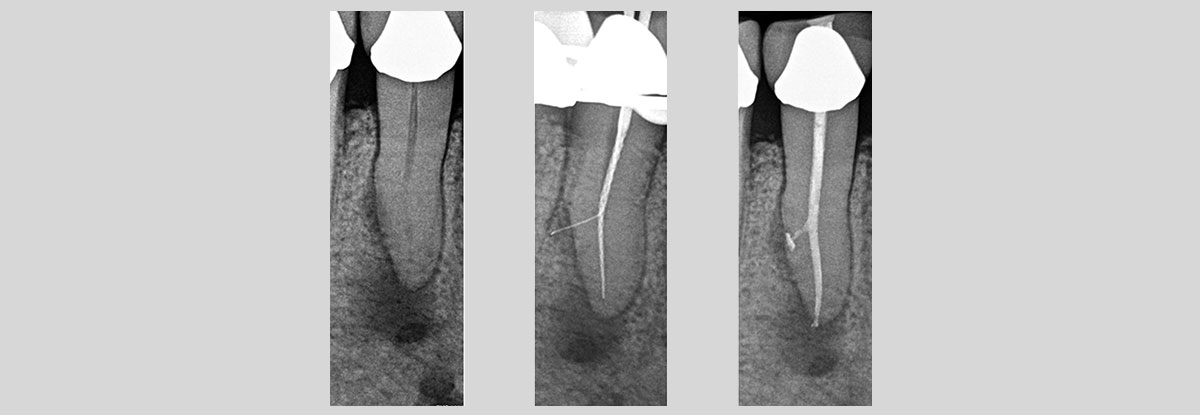

At our centre, we use the latest equipment and state of the art treatment to give you a painless experience of root canal. We also try and do as conservative treatment as possible. One of our specialities is single sitting root canal treatment.

PROCEDURE :

Step 1

• Local Anesthesia is administered, after which Endodontist removes infection from the canals.

Step 2

• Cleaning and shaping of canals is carried out along with irrigation with sodium hypochlorite.

Step 3

• This protocol is followed till the root apex and ultimately the canal is sealed with gutta percha.